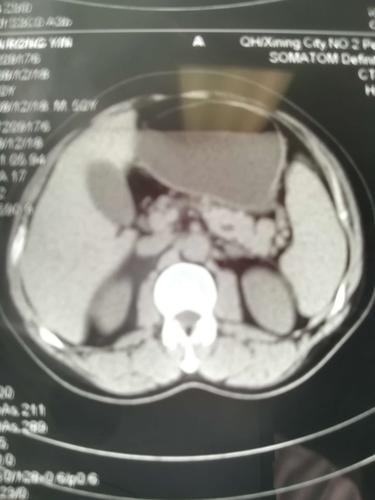

患者中老年男性,诊断:左侧腰疝